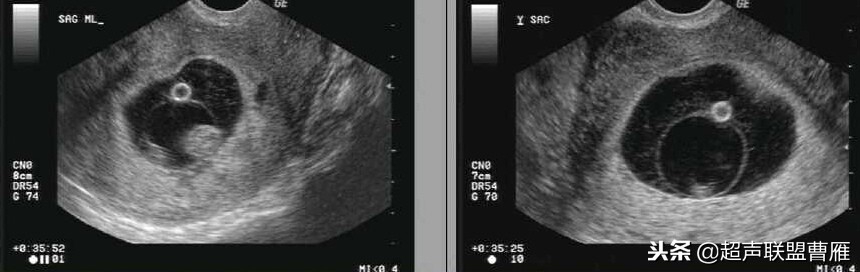

最大卵黄囊(5周)(12周)

卵黄囊11*6.9mm 大卵黄囊

卵黄囊消失

卵黄囊 羊膜囊 小胎儿雏形 (卵黄囊直径8.5mm)

卵黄囊回声增强,预后不良

卵黄囊钙化

卵黄囊过小2mm

卵黄囊不规则内有回声